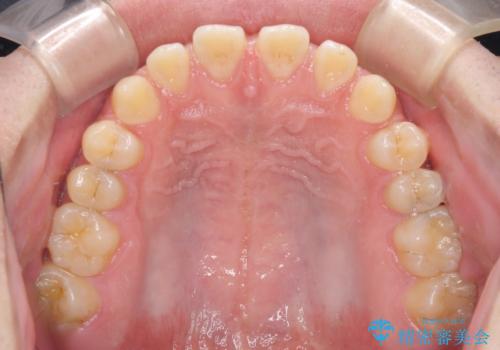

- 上下前歯の隙間を気にして来院された患者様です。

飲み込みや話をするときに舌を突出させる癖が強くあり、それが原因でスペースが空いていました。

装置除去後もトレーニングを継続されているようで、後戻りによるスペースは今のところ認められておりません。